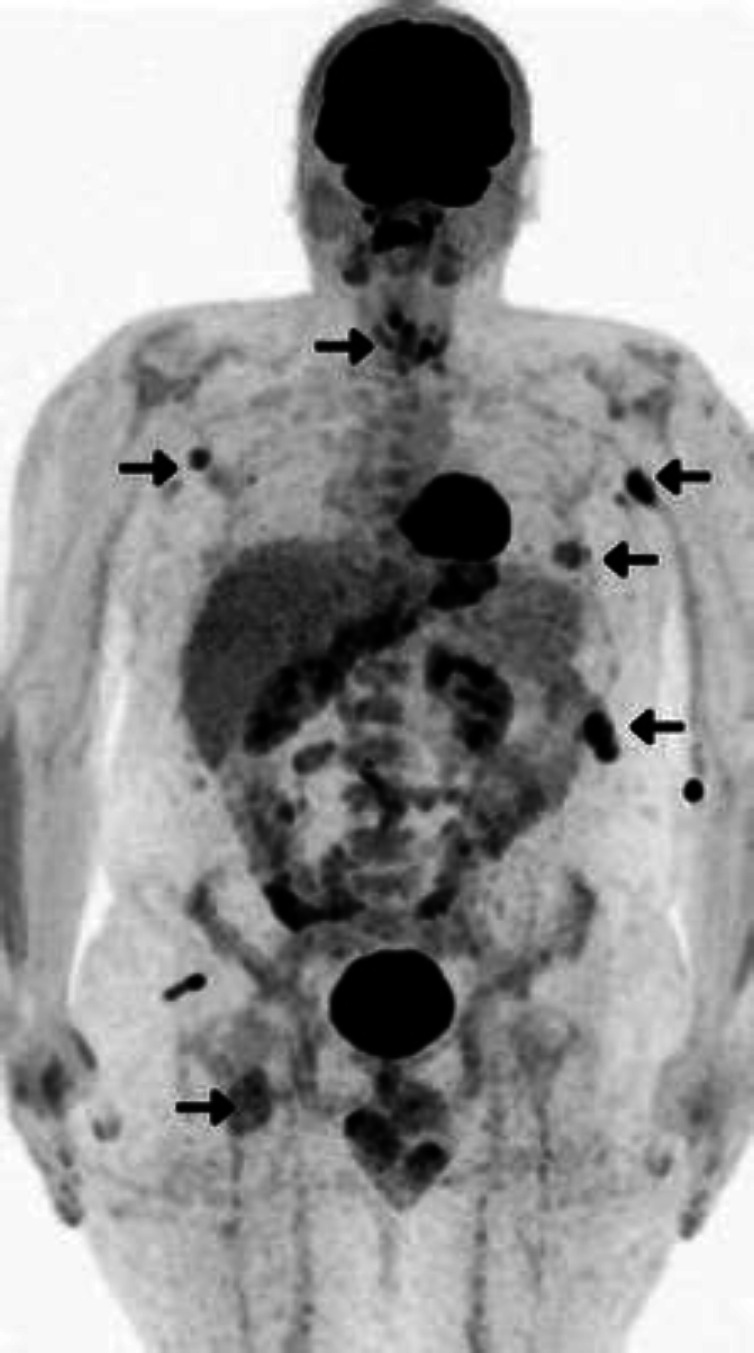

恶性周围神经鞘瘤(MPNST)是一种罕见的侵袭性软组织肉瘤,源于周围神经,往往给诊断和治疗带来挑战。恶性神经鞘瘤(MPNST)可能偶发,也可能与 1 型神经纤维瘤病(NF1)伴发,NF1 是一种由 NF1 基因突变引起的遗传性疾病。本报告介绍了一例独特的病例,患者是一名 33 岁男性,患有进行性干咳、声音嘶哑和颈部肿胀,接受了甲状腺全切除术,发现甲状腺内有一个高级别恶性周围神经鞘瘤。经 FDG PET/CT 检查,最终确诊为 NF1。由于在甲状腺内发现 MPNST 并同时发现 NF1 的罕见性,该病例显得尤为突出。它强调了对MPNST患者进行NF1筛查的重要性,反之亦然,突出了FDG PET/CT在综合评估中不断扩大的作用。据我们所知,本报告是全球首例NF1相关的甲状腺受累的MPNST病例。

Malignant peripheral nerve sheath tumors (MPNST) are rare, aggressive soft tissue sarcomas that arise from peripheral nerves and often present a diagnostic and therapeutic challenge. They can occur sporadically or in association with neurofibromatosis type 1 (NF1), a genetic disorder caused by mutations in the NF1 gene. This report presents the unique case of a 33-year-old male with progressive dry cough, hoarseness, and neck swelling who underwent a total thyroidectomy, revealing a high-grade malignant peripheral nerve sheath tumor invading the thyroid. FDG PET/CT led to the additional diagnosis of NF1. This case stands out due to the rarity of finding an MPNST within the thyroid and the simultaneous identification of NF1. It underscores the importance of screening MPNST patients for NF1 and vice versa, spotlighting the expanding role of FDG PET/CT in comprehensive evaluations. To our knowledge, this report presents the first case of NF1-associated MPNST with thyroid involvement worldwide.